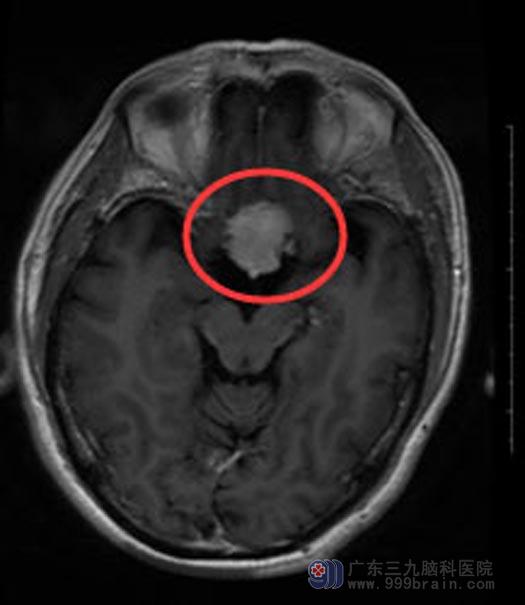

近半个月来,吴叔不仅视物模糊症状加重,还伴有频繁的头晕头痛。在广东三九脑科医院,头颅MR检查结果提示“1.鞍结节占位性病变,考虑为脑膜瘤,2.右侧筛窦炎症”。

手术前